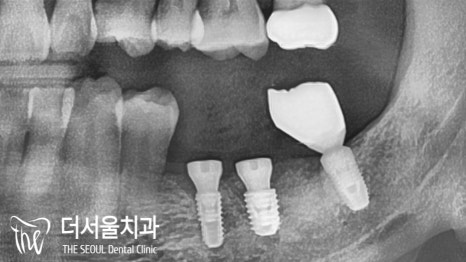

컴퓨터분석임플란트 를 심기 전,

내부 조직과의 위치 관계를 확인해야겠죠?

상악은 상악동~

하악은? 하치조신경관~

초록색 선이 신경관의 위치입니다.

어? 그런데 제가 잘못봤나요..

신경관이 앞에 떡하니…

이럴 땐 더더욱 컴퓨터분석임플란트 를 해야 됩니다.

정확한 위치 및 거리 계산을 통해

단 0.001mm의 오차도 발생하지 않도록 진행을 해야 되죠.

자칫 삐끗했다간 신경관 손상 및 마비로

이어질 수 있는 큰 문제이기 때문이죠.

미리 결정된 식립 위치에 맞춰

컴퓨터분석임플란트 식립을 마무리 했습니다.